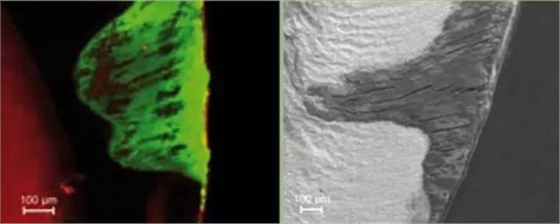

樹脂滲透技術(shù)首先使用酸蝕劑將表層的再礦化區(qū)去除,打開樹脂滲透的通路,同時使用干燥劑將孔隙中的水分去除,然后使用高滲透系數(shù)的滲透樹脂(滲透系數(shù)與表面張力和接觸角及粘度密切相關(guān)),滲透進入脫礦形成的微孔中,然后光照固化,阻塞脫礦區(qū)同外界相通的通道,終止脫礦離子的繼續(xù)流出及外界酸性物質(zhì)的繼續(xù)進入。

樹脂滲透技術(shù)不同于其他齲病治療方法,不是將病變?nèi)コ?,而是終止病變的繼續(xù)發(fā)展,同時滲透進入釉質(zhì)脫礦微孔后的樹脂在一定程度上可以增強脫礦區(qū)的強度。由于滲透樹脂的遮光性是1.52,因此與釉質(zhì)的折光率接近,從而使脫礦區(qū)與正常釉質(zhì)的顏色接近[15-16]。后者是樹脂滲透技術(shù)的附帶作用,但是恰恰可以改變光滑面脫礦區(qū)的顏色,改善美學效果。